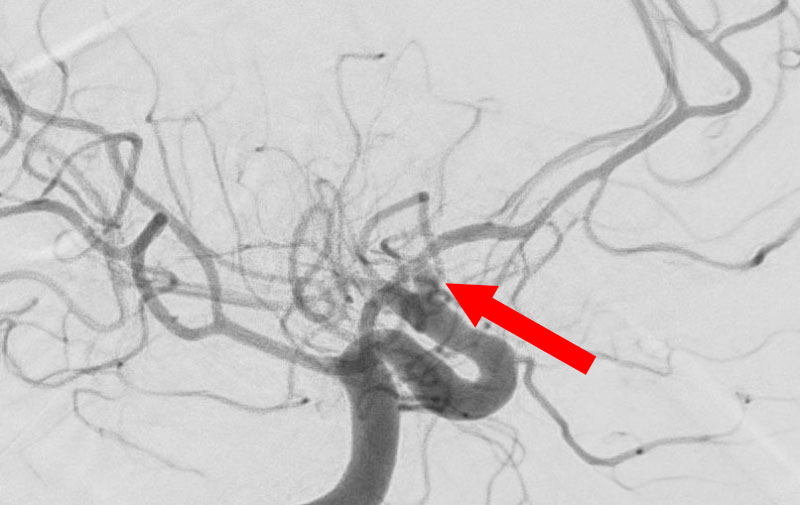

'25年10月

くも膜下出血

前交通動脈瘤破裂

60代

救急外来

No.1588 手術前

No.1588 手術中

No.1588 手術後